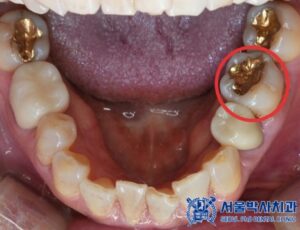

위 환자분은 전체적인 구강 검진을 위해

집 근처에 있는 저희 치과를

방문하셨는데요.

자연치아를 살리는 방향으로

치료를 받고 싶다고 하셨습니다.

먼저 전체적인 검진 결과,

왼쪽 아래 큰 어금니 부위에서

금 인레이 아래쪽으로 이차 충치와

염증이 발견되었습니다.

해당 치아는 신경 치료가

필요한 상태였기 때문에

서울박사치과에서는

자연치아 보존을 최우선으로 하는

“MTA 신경치료”를 진행하기로 하였습니다.